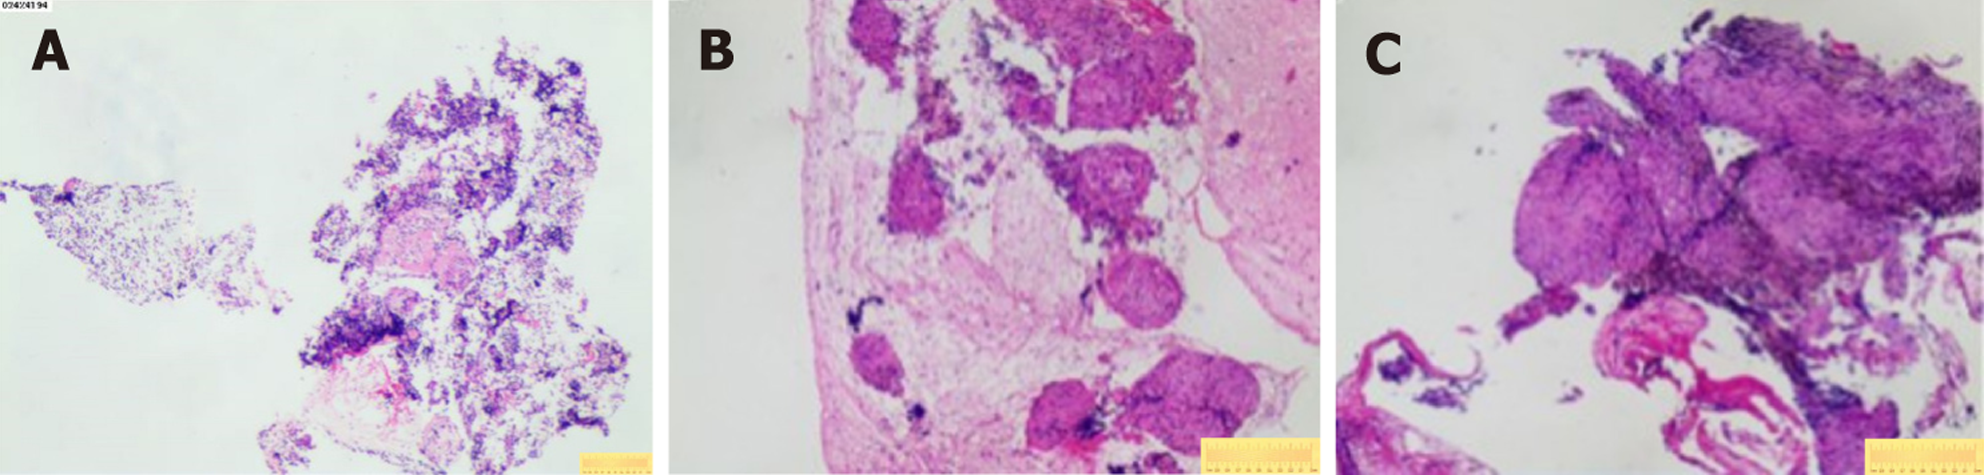

Case 1: Bronchoscopic lavage (June 7, 2024) showed no tumor cells. There were no remarkable results in initial diagnostic evaluations, including routine blood tests, erythrocyte sedimentation rate, biochemistry, coagulation profile, cardiac markers, and serum tumor markers. A repeat procedure was performed on July 1, 2024, under informed consent due to inconclusive findings from the previous bronchoscopy. Bronchoalveolar lavage fluid analysis showed no pathogens but a lymphocyte count of 12002/μL and a CD4/CD8 ratio of 5.81. A biopsy of the right upper lobe apical segment lesion was obtained, followed by EBUS-TBNA using an Olympus 21-G needle to sample station 7 Lymph nodes and posterior upper tracheal soft tissue (Figure 1). Subsequently, EBUS-TBFB was conducted by inserting a 1.2-mm fine biopsy forceps through the pre-established 21-G puncture site under real-time ultrasound guidance. As a result, 4-6 mediastinal biopsies with specimens ≥ 3 mm in diameter were obtained. No post-procedural bleeding was observed. There were scattered epithelial cells, inflammatory infiltrates, and multinucleated giant cells, but no atypia or granulomas in the histopathological analysis of EBUS-TBNA specimens, whereas EBUS-TBFB samples confirmed non-caseating granulomas with multinucleated giant cells (Figure 2A). Immunohistochemistry demonstrated Cytokeratin pan (epithelial+), CD68 (KP-1+), S-100 (−), and Ki-67 (high expression in inflammatory cells), while special stains for acid-fast bacilli, periodic acid-schiff, and Gomori methenamine silver were negative. Serum angiotensin-converting enzyme levels were elevated at 76.3 U/L.

Case 2: Initial diagnostic evaluations revealed thrombocytopenia (55 × 109/L) with normal coagulation parameters, biochemistry, tumor markers, and negative antinuclear antibodies. Pulmonary function tests indicated mild obstructive ventilatory impairment, while a nasopharyngeal biopsy demonstrated lymphoid hyperplasia. There was no remarkable abnormal phenomenon in fundoscopic examination, and a bone marrow biopsy performed on December 17, 2024, showed partial megakaryocyte maturation arrest without atypia or fibrosis. On December 19, 2024, bronchoscopy with bronchoalveolar lavage fluid analysis revealed a CD4/CD8 ratio of 4.68 under general anesthesia. Concurrently, EBUS-TBNA using an Olympus 21-G needle (three passes) and EBUS-TBFB were performed on subcarinal (station 7) lymph nodes via the same puncture site, adhering to the protocol described in Case 1. The EBUS-TBFB yielded specimens with a diameter of at least 3 mm. In accordance with the histopathological examination, non-caseating granulomas without necrosis were identified (Figure 2B and C), and serum angiotensin-converting enzyme levels were elevated at 51.1 U/L.